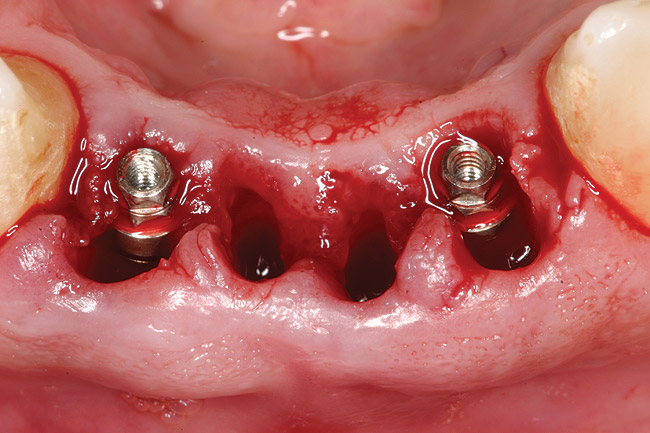

Figure 4  Implants were placed without flap elevation.

Figure 4

Figure 9  Stage 1 surgery.

Figure 9